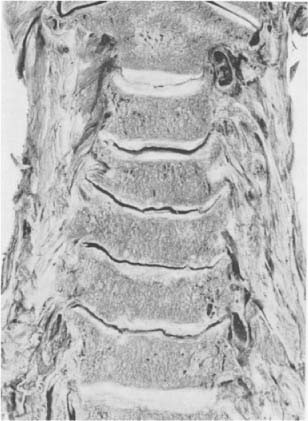

Halswirbelsäule eines 74jährigen Mannes. Bei der untersten Halsbandscheibe sind die Processus uncinati bis zur Horizontalen niedergelegt (Pfeile). Eine dünne Schicht von Faserknorpel vermag die Stöße nicht genügend zu dämpfen: Es kommt zu Sklerosierung nicht im Uncovertebralbereich, sondern in der ganzen Ausdehnung der Knochenendplatte (Skl)